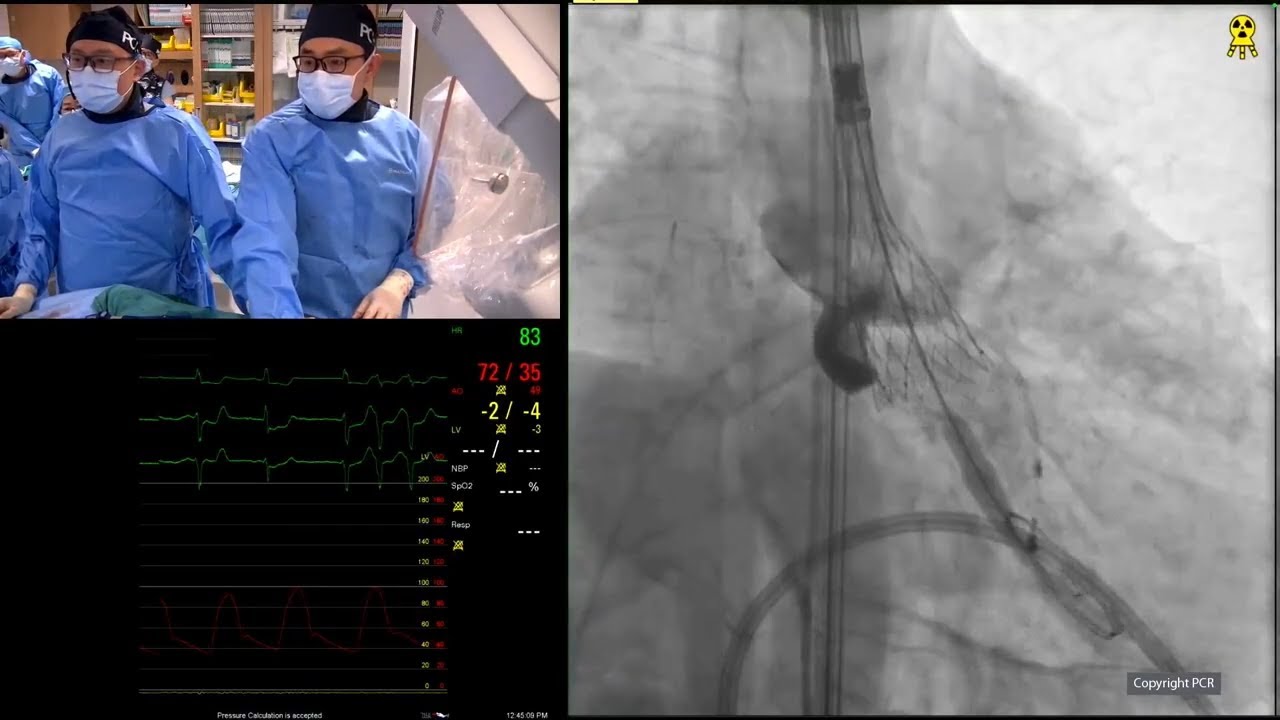

Redefining precision and performance in TAVI: advancing clinical outcomes with the Evolut FX+ system

Delve into advanced transcatheter aortic valve implantation (TAVI) with the Evolut FX plus system, focusing on its application in patients with small annulus and coronary artery disease (CAD). This session details step-by-step deployment, patient selection, imaging analysis, and highlights the distinctions from the previous Evolut R...